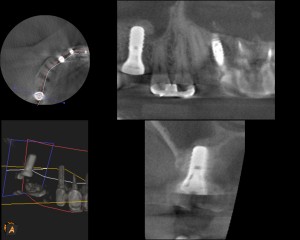

症例④

複数の歯に及び歯が失われているためCT画像上で診断と設計を行い、理想的な位置に歯を作ることができるように、サージカルガイドと言われるインプラント手術補助用マウスピースを用いてインプラント手術を行った。

-

手術の精度を更に上げるサージカルガイド

術前CT

術後CT